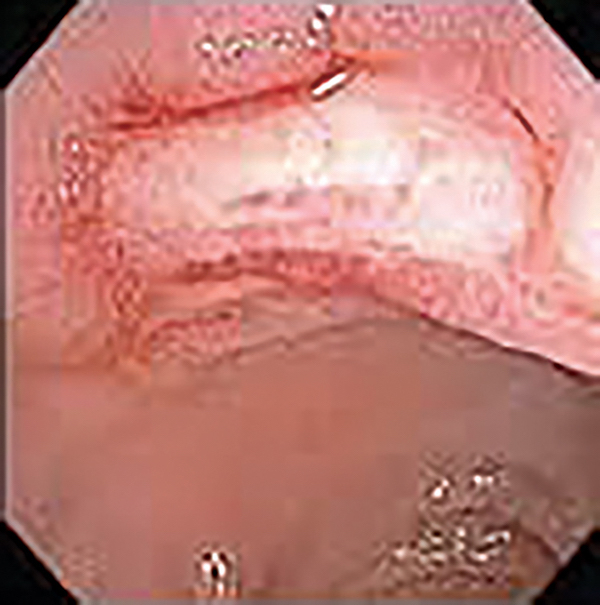

A 66-year-old woman is admitted to the hospital with a 1-day history of abdominal pain and hematochezia. Her prior medical history is notable for poorly controlled type II diabetes mellitus, hypertension, hyperlipidemia, osteoarthritis, glaucoma, and alcoholic cirrhosis. She drinks a half pint of alcohol per day and has done so for 30 years. She smokes 1 pack of cigarettes per day and uses cocaine 3-4 times per month. Her last cocaine use was 3 days prior to admission. She takes ibuprofen 400-800 mg 2-3 times a day as needed for pain. Admission laboratory tests results reveal WBC 9,500/µL, hemoglobin 10 g/dL, INR 2.1, hemoglobin A1c 13.4, FOBT positive, C. difficile negative. She is observed in hospital and prepared for colonoscopy, which reveals the lesion shown in FIGURE A. Biopsy of this lesion is shown in FIGURE B. Which of the following therapies is most appropriate for this condition?

The patient has “colon ischemia” or “ischemic colitis.” This is clear from the description of the presentation, which is classic for this disease state. The patient also has the most significant risk factor for colon ischemia, which is COPD. Finally, the image shows the “single stripe sign,” the colonoscopic finding most commonly associated with colon ischemia. The most common distribution of colon ischemia involves the left colon, specifically the rectosigmoid colon. The disease distribution is also importantly associated with severity of disease. Patients with isolated right colonic disease distribution are at the highest risk for poor outcome.